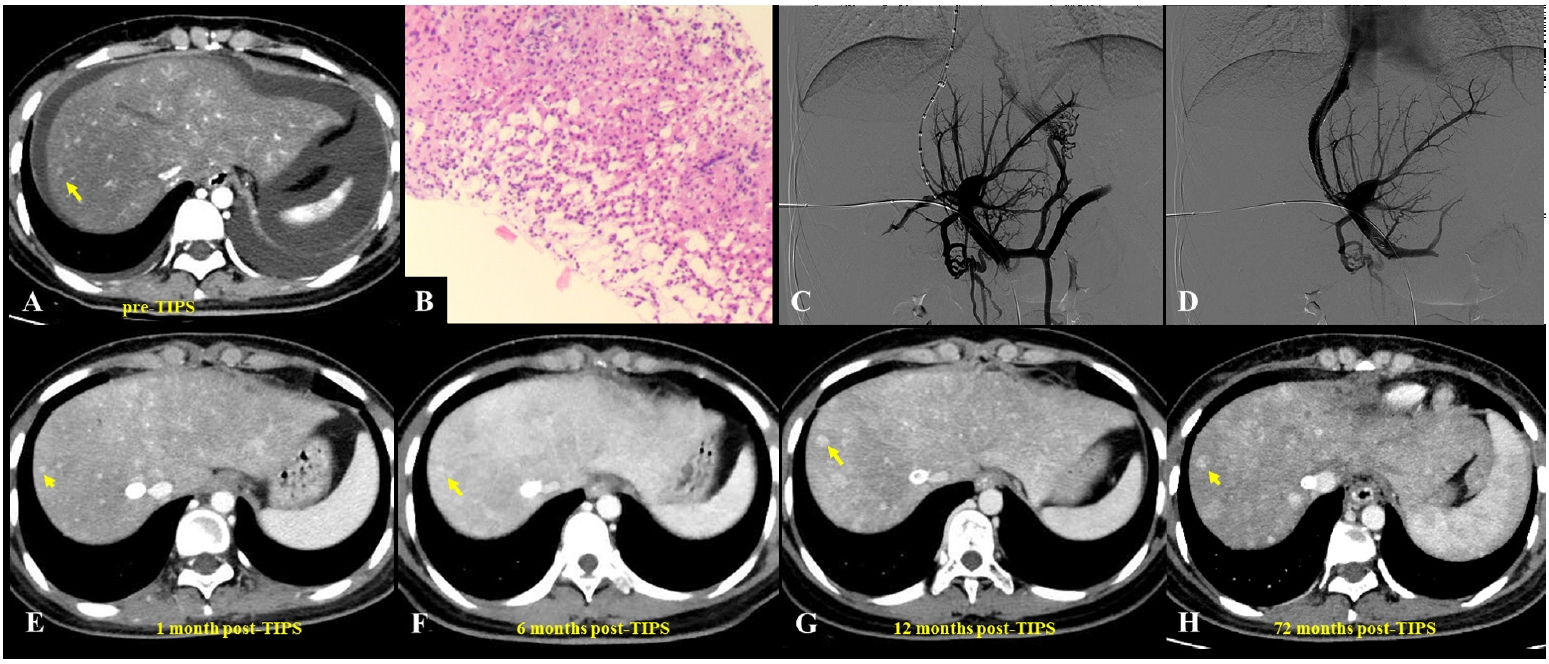

Fig. 2.A 23-year-old woman presented with pyrrolizidine alkaloid–induced hepatic sinusoidal obstruction syndrome following ingestion of oral weight-loss medications. (A) Pre–transjugular intrahepatic portosystemic shunt (TIPS) computed tomography (CT) (portal venous phase) demonstrated heterogeneous, patchy hepatic enhancement with multiple regenerative nodules (yellow arrow), accompanied by massive ascites and bilateral pleural effusions. (B) Histopathological analysis from a transjugular liver biopsy revealed focal hepatic atrophy, marked sinusoidal dilatation, and hepatocellular cholestasis, consistent with hepatic venous outflow obstruction. Immunohistochemical staining was negative for hepatitis B surface antigen, hepatitis B core antigen, diastase-periodic acid-Schiff, and periodic acid-Schiff, while showing positivity for cytokeratin 7 (biliary epithelium), reticulin, and Masson’s trichrome (indicating underlying fibrosis) (H&E, ×400). (C) Due to the diminished caliber (slenderness) of the portal vein, percutaneous transhepatic balloon-assisted TIPS placement was performed. Initial portal venography confirmed narrowing of the intrahepatic portal branches, stagnant portal flow, and the presence of prominent esophagogastric varices. (D) Post-TIPS venography demonstrated a widely patent shunt with unobstructed portal venous return and successful decompression of the varices. (E-H) Follow-up contrast-enhanced CT scans (venous phase) obtained at 1 month (E), 6 months (F), 12 months (G), and up to 72 months (H) post-TIPS demonstrated persistent heterogeneous enhancement and intrahepatic nodules (yellow arrows).

TIPS has emerged as an important therapeutic option for PA-HSOS patients with refractory PH or ascites, and although it has no specific contraindications for treatment, guidelines recommend considering it for patients with ineffective medical therapy, highlighting the importance of individualized assessment [

15]. Studies have shown that ascites and pleural effusions can markedly improve within a short period after TIPS placement, with previously obstructed hepatic veins often regaining patency in the short term when combined with AT (

Figs. 1,

2) [

10,

52]. Various studies have confirmed the safety and efficacy of TIPS in managing PA-HSOS (